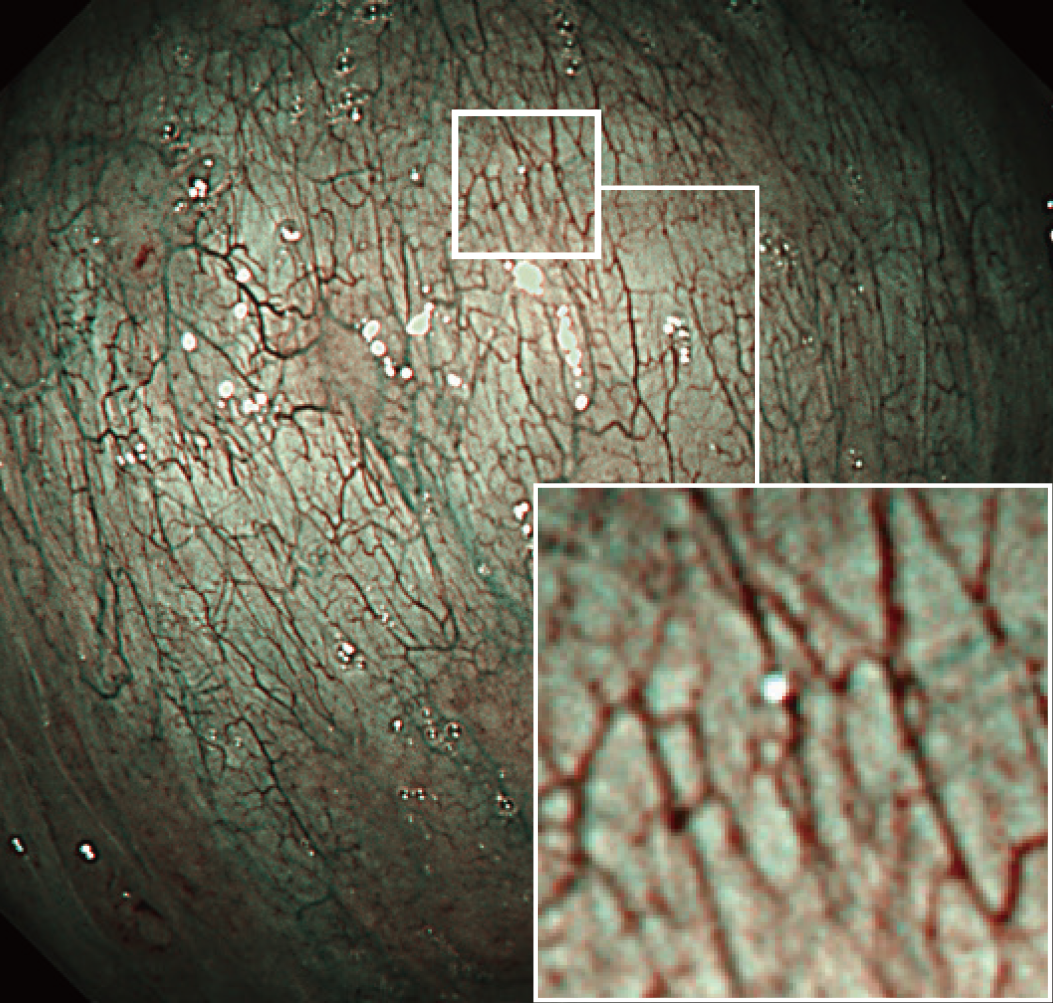

低ノイズハイビジョン画像

新しく開発されたCMOSイメージセンサーによりノイズの少ないハイビジョン画像を実現しました。また、改良された光学系と、高精度のレンズ組み立て技術の確立によって、明るさを確保し、微細な血管や粘膜の表面もリアルに再現することが可能となり、正確な診断をサポートします。

NBI近接観察